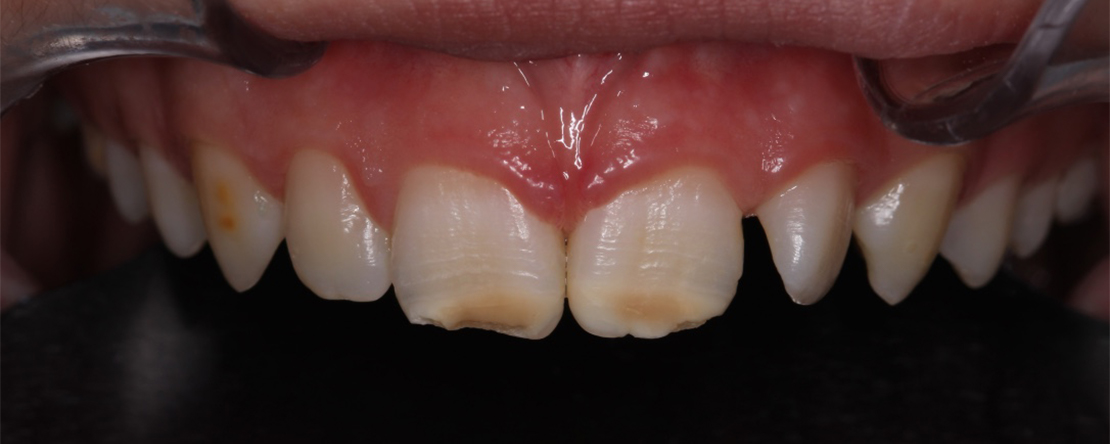

Como abordar uma condição dentária que torna os dentes mais sensíveis, frágeis e propensos à cárie, e que desafia os métodos restauradores tradicionais? Nesta apresentação sobre Hipomineralização Molar-Incisivo (HMI), vamos explorar o papel central do médico dentista na gestão desta patologia. Como diagnosticar precocemente a HMI, garantindo que as crianças recebam os cuidados necessários antes que as complicações se instalem? Quais as estratégias preventivas mais eficazes e como melhorar a qualidade de vida destas crianças?

Para além da prevenção, a HMI envolve desafios restauradores significativos. A fragilidade do esmalte hipomineralizado, a sensibilidade dentária e as dificuldades de adesão, aliadas frequentemente a implicações no controlo comportamental, constituem relevantes barreiras ao tratamento. Que soluções restauradoras tem o odontopediatra ao seu dispor? Desde as resinas compostas e coroas para casos mais severos, até técnicas inovadoras como as resinas infiltrativas que oferecem uma abordagem minimamente invasiva e estética.